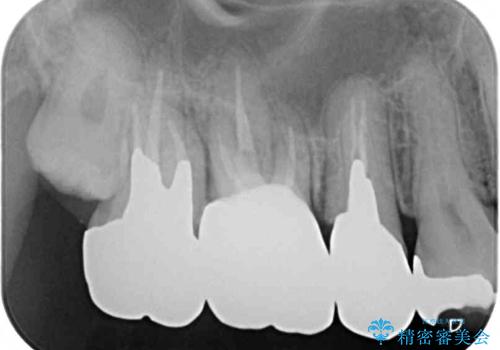

- ものが挟まるとのことで来院された患者様です。

一度は治療せずに放置していましたが、1年後のメインテナンスの際に悪化していることが分かったことから、補綴治療を行うこととしました。

神経を抜いてある歯はむし歯が進行しても痛みを感じることがないため、気がついたときには著しくむし歯が進行している可能性があります。

早めの対応とすることで、抜歯を回避できることはもちろん、外科処置などの本来必要のない処置を行わずに対処することができました。